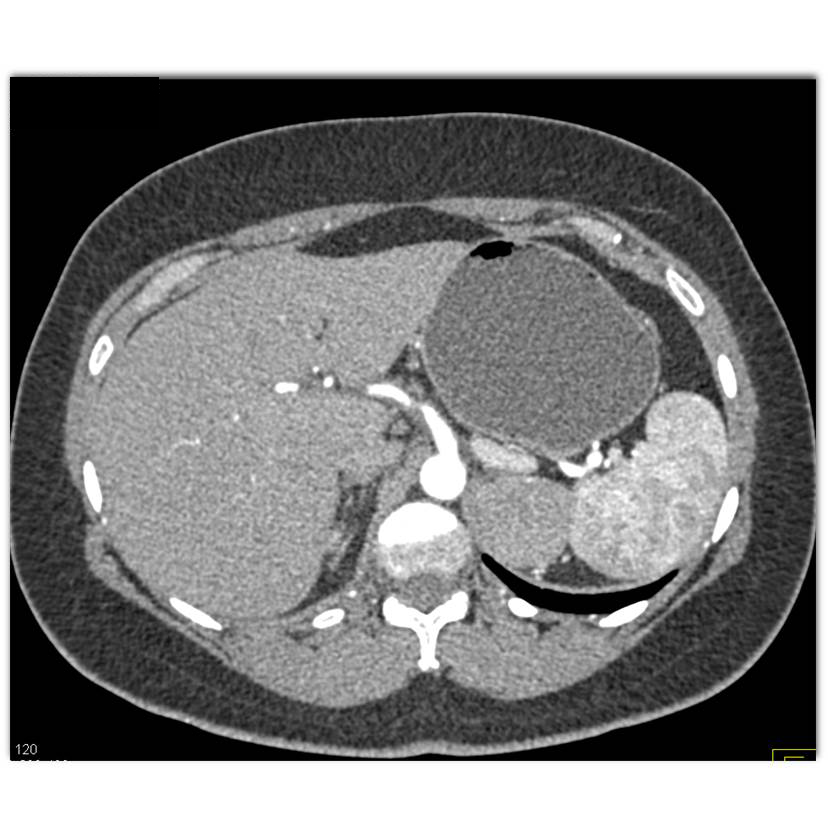

The least likely diagnosis for this 5cm left adrenal mass is?

adrenal adenoma

adrenal carcinoma

pheochromocytoma

adrenal lymphoma